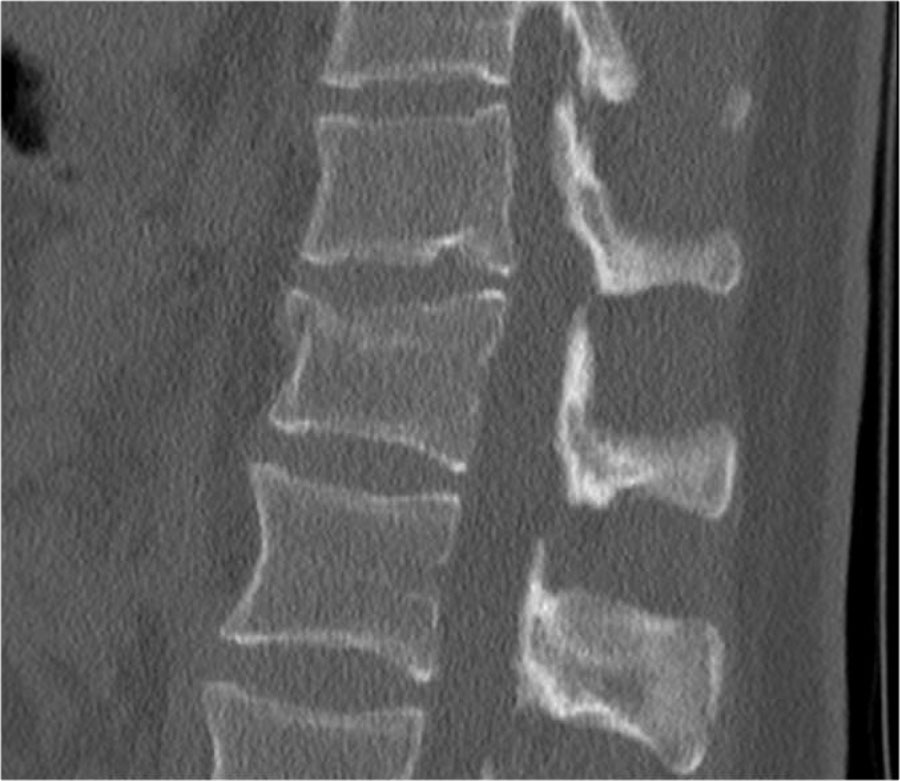

Các hình ảnh cho thấy một trường hợp gãy xương nén.

Dấu hiệu duy nhất quan sát được là sự gián đoạn vỏ xương ở thành trước trên của thân đốt sống và mất chiều cao nhẹ ở phía trước.

Vỏ xương phía sau thân đốt sống còn nguyên vẹn.

Hình tái tạo mặt phẳng đứng dọc cũng cho thấy sự gián đoạn vỏ xương.

Lưu ý rằng trên lát cắt axial dày 2,5mm, có thể bỏ sót các gãy xương này.

Cần xem xét các lát cắt mỏng để phát hiện những gãy xương tinh tế như vậy.